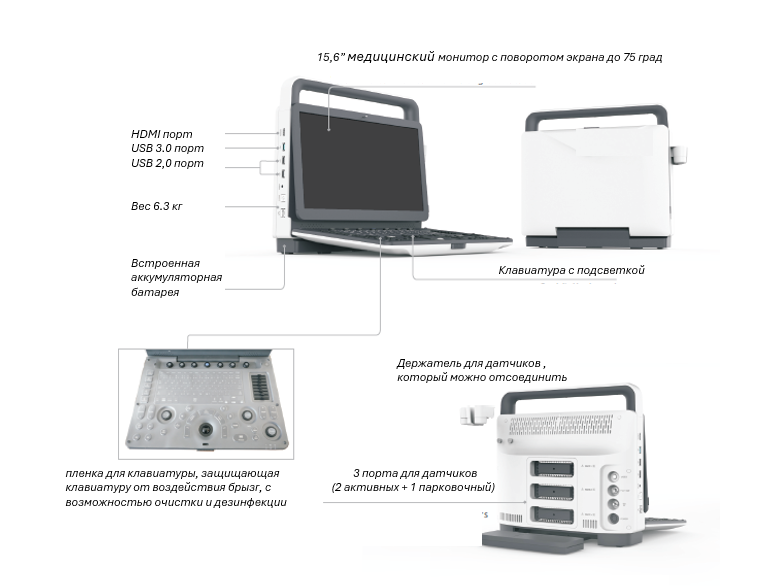

Специальный дизайн для ветеринарии

Портативные сканеры легкие (5-15 кг) и компактные (размером с ноутбук), активно применяются в ситуациях, требующих скорой медицинской помощи, как на выездах, так и внутри лечебного учреждения. В больнице переносные приборы часто устанавливаются на специальную тележку, оснащенную держателями датчиков и другими опциями.

- Портативный

Портативные сканеры, как правило, имеют один-два порта и подходят для проведения узкоспециализированных исследований одним-двумя датчиками, например, при оказании экстренной медицинской помощи или при использовании в операционной.

В комплект входят тележка, кейс и ножная педаль